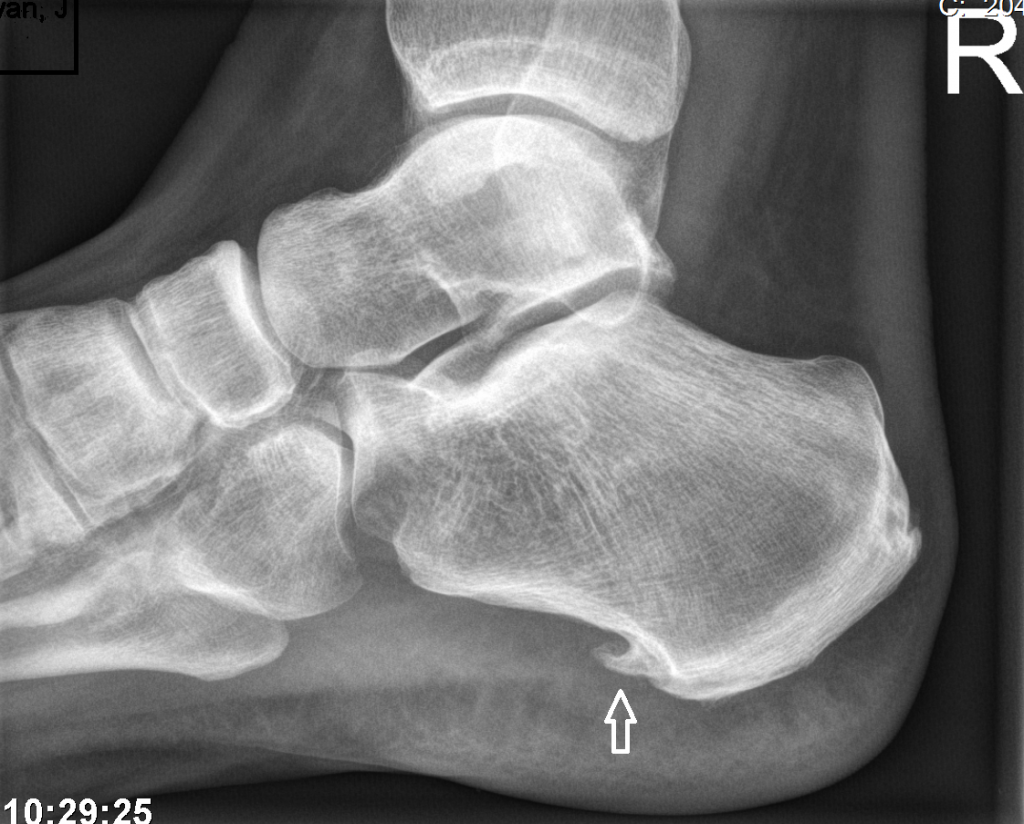

Een marsfractuur is pas 2 weken na de breuk zichtbaar op een röntgenfoto. Als u dus meteen na de wandeling veel pijn heeft en een röntgenfoto laat maken, zal de breuk niet meteen zichtbaar zijn. Dit komt omdat de scheurtjes vaak klein zijn en na 2 weken is er pas zichtbaar dat er extra bot wordt aangemaakt op de plek van de kleine breuk. (zie afbeelding onder)

Bij Podologie Arnhem, maken de podoloog meteen een echo, waardoor we sneller een diagnose kunnen stellen. De podoloog zal u adviseren om tijdelijk niet, of zo weinig mogelijk te wandelen. Ook zal hij een steunzool maken om de aangedane plek drukvrij te leggen.